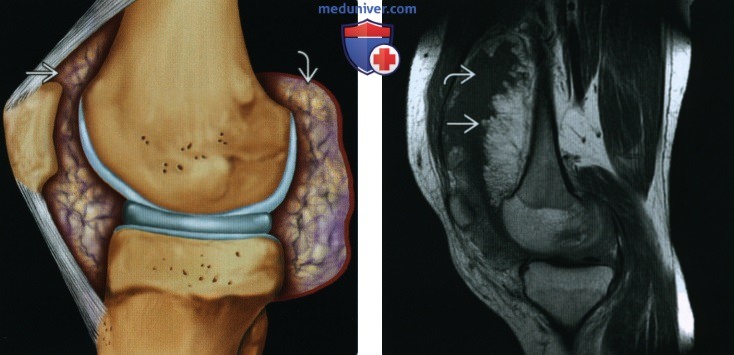

(Слева) Рисунок, сагиттальный срез: диффузная ворсинчатая жировая инфильтрация синовиальной оболочки всего сустава. Это приводит к растяжению суставной капсулы как в передних, так и в задних отделах сустава.

(Справа) МРТ Т1 ВИ, сагиттальный срез: определяется выраженное растяжение суставной сумки коленною сустава, обусловленное жировой пролиферацией (гиперинтенсивный сигнал) синовиальной оболочки и гипоинтенсивным суставным выпотом. Обратите внимание на листовидный многодольчатый папиллярный характер внутрисуставных жировых объемных образований.